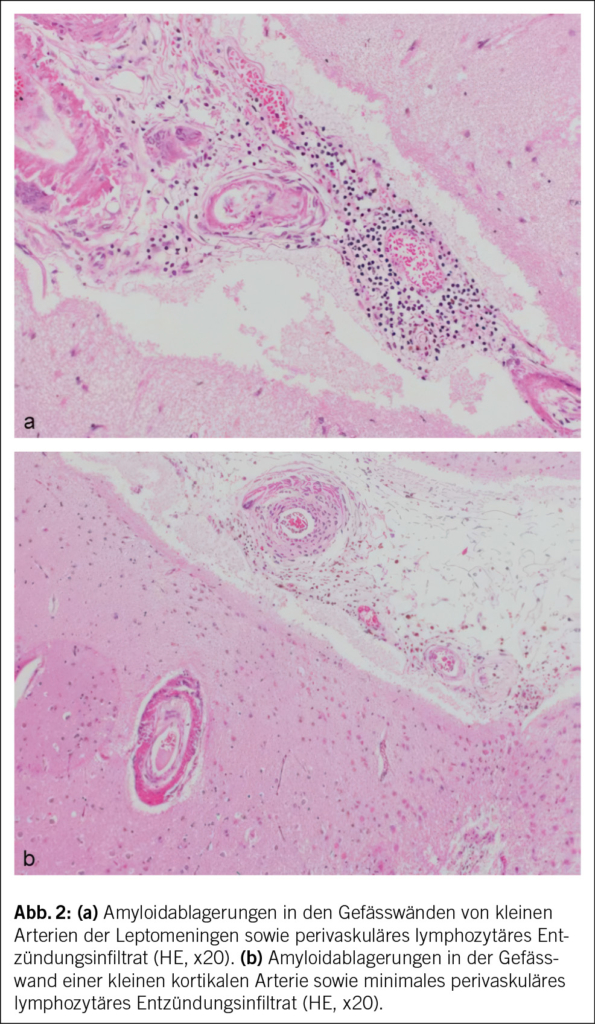

In Rücksprache mit den Angehörigen wurde bei infauster Prognose schliesslich eine palliative Therapie eingeleitet, und der Patient verstarb auf der Palliativstation am 10. Hospitalisationstag Ende Oktober 2020. Die Autopsie bestätigte schliesslich die Diagnose einer CAA-RI aufgrund einer deutlichen Beteiligung der Gefässe in den Leptomeningen und im Cortex, mit fokal geringer begleitender T-lymphozytärer Entzündungsreaktion sowie zahlreichen kortikalen Infarkten und perivaskulären Mikroblutungen (Abb. 2). Die CAA-RI führte über Gefässverschlüsse zu einer diffusen vaskulär-ischämischen Leukenzephalopathie und mehreren frischen und älteren, nicht raumfordernden Subarachnoidalblutungen. Das gesamte Bild sprach für eine CAA-RI und nicht für eine Beta-Amyloid-assoziierte Angiitis (ABRA), welche ein ähnliches histologisches Bild zeigt, jedoch mit ausgeprägter vaskulitischer Komponente und fibrinoiden Gefässwandnekrosen. Es zeigten sich dazu deutliche Alzheimer-assoziierte Veränderungen mit Tau-positiven Neurofibrillendegeneraten und neuritischen Plaques im Hippocampus und Temporal-Cortex und vereinzelt Tangles im frontalen Cortex (Stadium IV nach Braak und Braak, CERAD-3 und ABC-Score A3 B2 C3), dies bei deutlicher äusserer und innerer Hirnatrophie. Zudem fand sich überraschenderweise ein Hämatom der vorderen Bauchwand mit einem Volumen von ca. 1500 ml, und es wurde eine Lobärpneumonie beider Lungen diagnostiziert. Ob die Pneumonie ursächlich für die bislang unklare CRP-Erhöhung war oder die Infektion in den letzten Lebenstagen auf der Palliativstation entwickelt wurde, konnte nicht abschliessend geklärt werden. Die Ätiologie des Hämatoms blieb letztlich unklar. Histologisch fanden sich hier keine Hinweise auf eine Gefässmalformation, Amyloidangiopathie oder Vaskulitis. Ein stumpfes Trauma wurde in der aktuellen Hospitalisation nicht beobachtet, der Patient war nicht antikoaguliert, und während der letzten Hospitalisation erfolgten keine Massnahmen abdominal (z. B. Insulin- oder Heparinspritzen). Nicht eruierbar waren mögliche Vorfälle in den vorangehenden Institutionen. Abdominale Blutungen bei Patienten mit CAA-RI wurden bisher nicht als Assoziation beschrieben. Als Todesursache wurde ein kardiopulmonales Versagen aufgrund der Pneumonie sowie Volumenmangel aufgrund des Hämatoms angegeben.

Die Amyloidablagerungen sind bei einem Teil der Patienten mit einer Entzündung der Gefässwand vergesellschaftet, was schliesslich zu einem multifokalen Marklagerödem führt. Insgesamt zeigen diese Veränderungen im MRI ein typisches Bild, welche für die Diagnosestellung einer CAA-RI wesentlich sind. Die Veränderungen lassen sich vor allem in der FLAIR-Sequenz (fluid attenuated inversion recovery) und bei der SWI (Suszeptibilitätsgewichtete Bildgebung) feststellen (2, 3). Dazu gehören Mikroblutungen, eine kortikale superfizielle Siderose und eine asymmetrische fleckförmige oder konfluierende Leukenzephalopathie, welche den angrenzenden Kortex und das subkortikale Marklager miteinbeziehen können. Ebenfalls kann sich als Zeichen der entzündlichen Reaktion ein vasogenes Ödem in der ADC- (apparent diffusion coefficient) Wichtung präsentieren (2, 4, 5). Es wurden die sogenannten modifizierten Boston-Kriterien entwickelt, welche auf eine gute Sensitivität und Spezifität geprüft wurden (6) (Tab. 1) und bei der Diagnosesicherung helfen. Zusätzliche klinische Diagnosekriterien sind ein akuter/subakuter Symptombeginn, Alter über 55 Jahre, Symptome wie Kopfschmerzen, Wesensveränderungen, kognitive Defizite oder fokal neurologische Defizite oder epileptische Anfälle. Andere Ursachen (z. B. infektiös oder paraneoplastisch) müssen ausgeschlossen werden. Sind alle diese Kriterien erfüllt, gilt eine CAA-RI als wahrscheinlich. Zur definitiven Diagnosesicherung wird eine histologische Bestätigung im Rahmen einer Autopsie benötigt, wobei sich neben frischen und alten Ischämien und Einblutungen auch entzündliche, perivaskuläre Veränderungen ohne Gefässbeteiligung finden lassen. Hier kann eine Unterscheidung zur Beta-Amyloid-assoziierten Angiitis (ABRA) gemacht werden, welche ausgeprägtere vaskulitische Veränderungen und fibrinoide Gefässwandnekrosen zeigt. Diese erheblichen Zerstörungen des Hirnparenchyms direkt durch invasive zytotoxische T-Lymphozyten und indirekt durch vaskulitische oder begleitthrombotische Gefässverschlüsse bedingen eine stärkere Immunsuppression als bei der CAA-RI. Teils wird in der Literatur jedoch die ABRA synonym zur CAA-RI genannt. Ob eine Histologie zur Diagnosestellung einer CAA-RI immer zwingend ist, steht aktuell immer noch zur Diskussion. Eine genaue Diagnose hat jedoch teils therapeutische Konsequenzen. Vor allem bei fehlendem Therapieansprechen sollte eine Biopsie angestrebt werden.